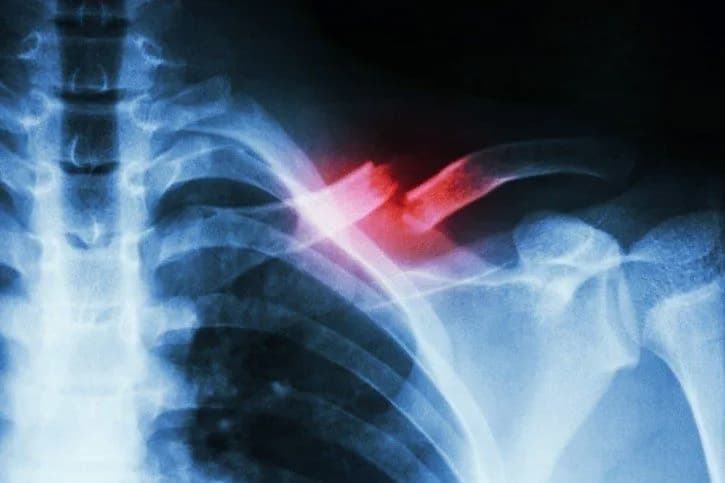

Ile trwa rehabilitacja po złamaniu obojczyka i jak uniknąć bólu?

Ile trwa rehabilitacja po złamaniu obojczyka? Dowiedz się, jak długo trwa proces zdrowienia i jak uniknąć bólu podczas rehabilitacji.